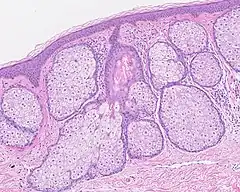

Multiples glandes sébacés volumineuses réalisant une hyperplasie sébacée.

- L'hyperplasie sébacée (voir Sebaceous hyperplasia (en)), se référant à une prolifération excessive des cellules dans les glandes, et visible macroscopiquement sous forme de petites papules sur la peau, particulièrement sur le front, le nez et les joues[28].